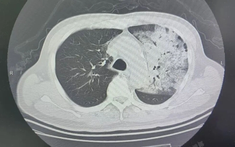

phổi trắng

Người đàn ông sốt 40 độ C, phổi gần như 'trắng xóa", chỉ vài ngày đã suy đa tạng: Thủ phạm liên quan đến thói quen nhiều gia đình vẫn mắc

Một bé trai 12 tuổi nhiễm cúm A chủng H3N2, chỉ sau 24 giờ hình ảnh phổi đã xuất hiện tình trạng viêm lan tỏa nghiêm trọng, còn gọi là “phổi trắng”.